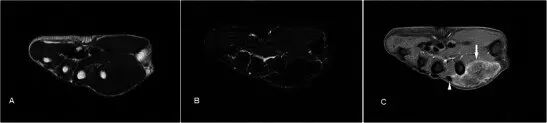

血管瘤 Haemangiomas 血管瘤是第四最常见的手部肿瘤,通常发生在年轻的年龄组,有轻微的女性优势[27]。在MR上,它们通常在T2w序列上非常高信号,并且显示出小叶,间隔或低信号灶比其他软组织块更频繁[28]。 T2w序列上损伤的标记高度信号是由于血管中停滞血流量增加的流体含量。 由于存在脂肪和血液成分,T1w序列上的信号通常与肌肉相比具有高信号(图8)。 通常大于2cm的损伤含有不同量的脂肪,平滑肌,粘液样基质,血栓和血铁素。上的GRE序列容易产生的假象可能是由于静脉石或血液成分引起,并且这些可以在平片进行区分。较大的病变也可能表现出流体 - 液体水平[29]。延时增强后瘤体趋于均匀强化。浅表性血管瘤易于诊断,因为皮肤褪色的存在,并且MRI可能仅需要评估其手术规划的程度。

图8.32岁女性血管瘤,沿着右手掌侧的内侧面呈现软肿块,偶尔会疼痛。 (a)T1w序列显示多发性皮下病变,小鱼际肌稍高信号肌肉,相邻肌腱(箭头)之间, 有一个小的肌肉内占位(箭头)。 (b)病灶在具有低信号(箭头)区域和流体 - 液体水平(箭头)建议的T2w-FS序列上是极度高信号的。 (c)看到显示静脉石或血制品(箭头)GRE序列。 (d)有积极和接近均匀的增强(箭头)